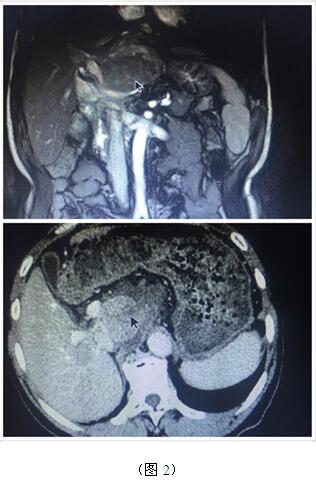

70歲高齡的曹奶奶是一個膽內(nèi)膽管結(jié)石、膽總管結(jié)石、膽囊結(jié)石的高齡患者,由于結(jié)石部位多發(fā)(圖1),當(dāng)?shù)蒯t(yī)院多次住院治療,均建議開大刀切除部分肝臟;同樣患肝臟腫瘤的張爺爺,由于腫瘤位于肝臟尾葉,而且壓迫腹腔大血管(圖2),尋遍多家醫(yī)院都只能開腹手術(shù)切除,聽說衡陽市中心醫(yī)院腹腔鏡手術(shù)技術(shù)成熟遂慕名而來。肝膽外科周玖橋主任和李鑫副主任醫(yī)師仔細(xì)分析病情后決定為倆位患者行3D腹腔鏡手術(shù)。